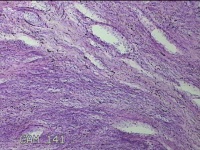

子宫体肌瘤结节

性别

女

年龄

32岁

临床诊断

子宫肌瘤 疤痕子宫

一般病史

发现子宫肌瘤数月余。

标本名称

大体所见

灰白色圆柱形条索状组织10x7.5x1.8㎝一堆,切面均为灰白色结节状或编织状,质中。